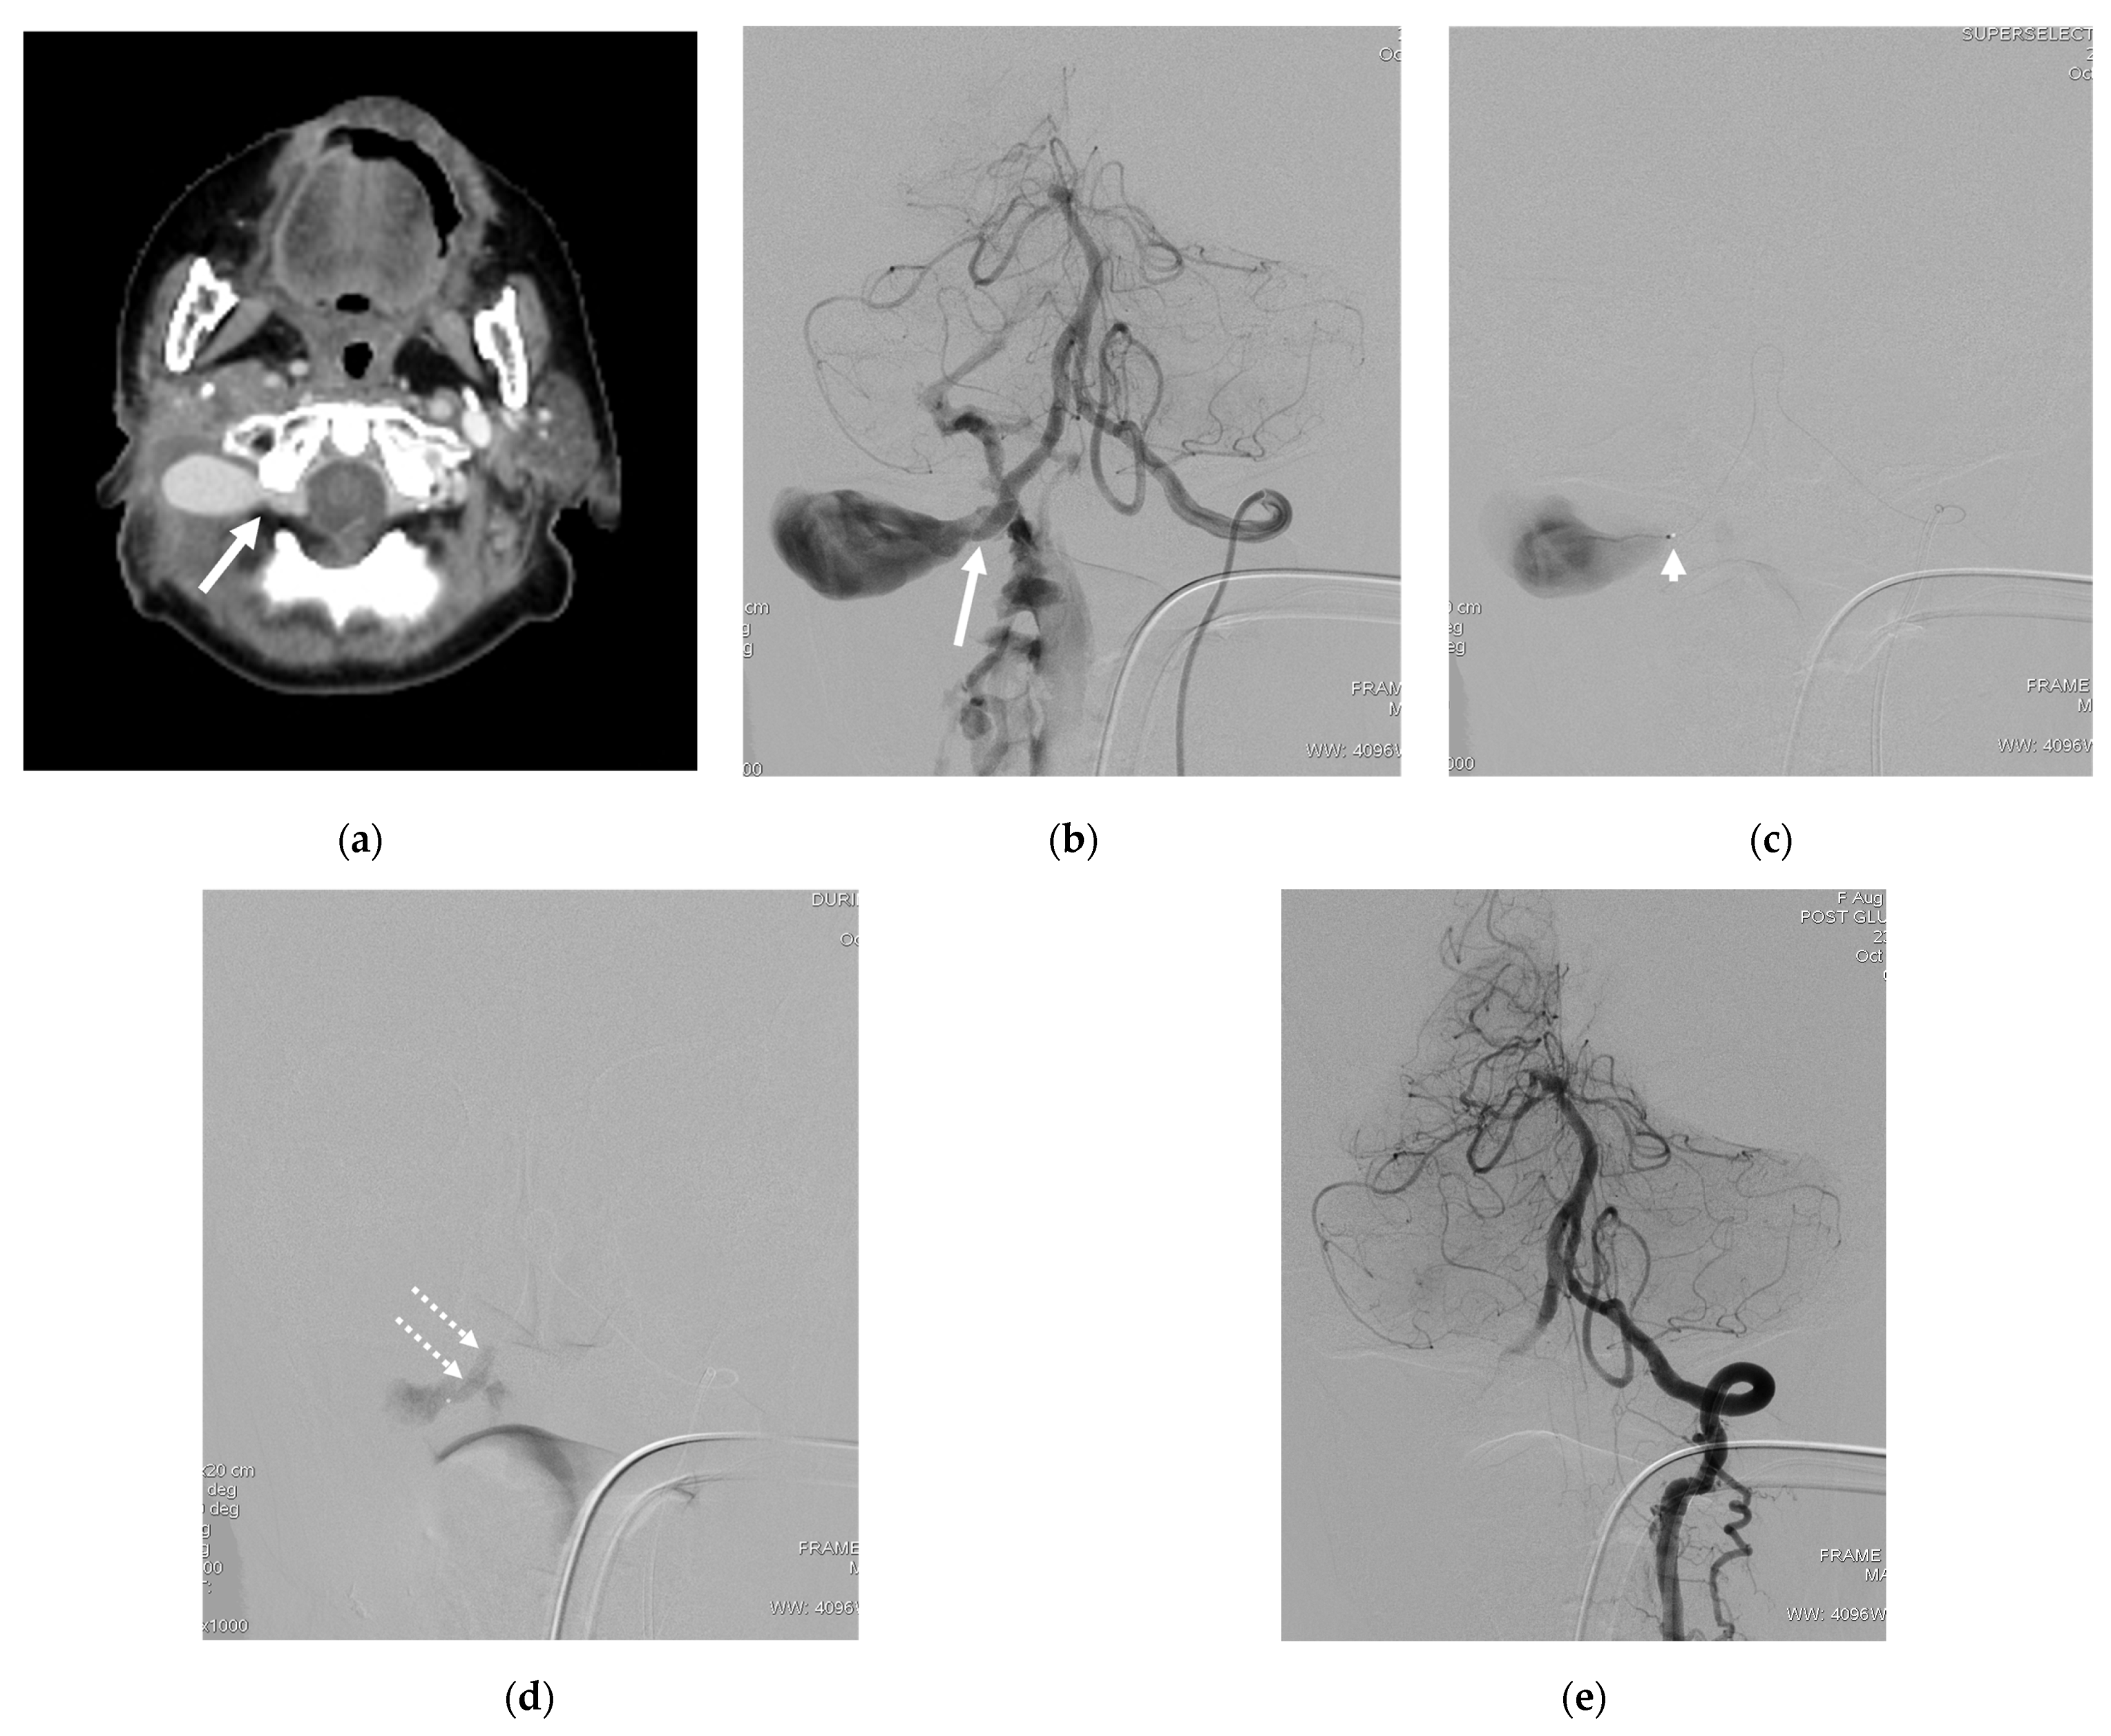

| 11 | F | 64 | Neck mass | Traffic accident | T | VVP with venous pouch | N | B | O | Improved | Transient occipital pain |

| 12 | F | 73 | Bleeding | Post-surgery | T | VVP with venous pouch | Y | NBCA | O | Improved | None |

| 13 | M | 57 | Neck mass; right arm weakness | Traffic accident | T | Radicular vein; IJV with venous pouch | Y | C | O | Improved | None |

| 14 | M | 36 | Bleeding in epidural space after surgery | Traffic accident | T | VVP with ruptured venous pouch in epidural space | N | B | O | Improved | None |